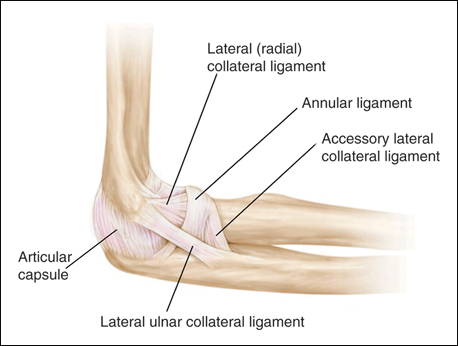

• associated with a traumatic elbow dislocation, and characterized by posterolateral subluxation or dislocation of the radiocapitellar and ulnohumeral joints.

• supination, axial loading, valgus (posterolateral) stress, and elbow extension causes progressive failure of the lateral collateral ligament complex and anterior capsule, resulting posterolateral subluxation of the radial head and external rotation of the semilunar notch away from trochlea

• L UCL primary stabilizer to varus & ER stress

The patient has sustained an iatrogenic injury to the lateral ulnar collateral ligament. This injury has been reported after lateral approaches to the elbow. The orbicular, annular, and lateral radial collateral ligaments have a much less important role in lateral elbow stability. The anterior band of the ulnar collateral ligament is on the medial side of the elbow and is important for valgus stability.